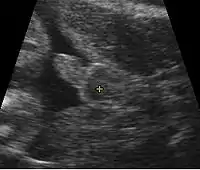

На 5-8 тиждень передбачуваної вагітності варто звернутись до жіночої консультації за місцем проживання і провести УЗД, яке дозволяє підтвердити місце |імплантації плідного яйця, аби виключити позаматкову вагітність; простежити серцебиття, аби виключити завмерлу вагітність, особливо за наявності ознак загрози переривання вагітності: важкості або болю внизу живота, кров'янистих виділень. Зазвичай, за наявності таких симптомів, через 3 дні призначається повторний наліз крові на ХГЛ — рівень гормону має подвоїтись, а також повторне УЗД — за два тижні. Якщо проявляються серйозні відхилення у стані ембріона чи матері, ставиться питання про можливість перервати вагітність.

В Україні обов'язкові УЗД при вагітності проводять у терміни 12, 24 та 36 тижнів. Також на 12 тижні необхідно стати на облік у жіночій консультації за місцем проживання. Тоді ж обов'язково проводять комплекс досліджень: